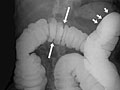

• In a single-contrast study, the colon is filled with barium. This outlines the intestine and shows large abnormalities.

• In a double-contrast or air-contrast study, the colon is first filled with barium, and then the barium is drained out. This leaves only a thin layer of barium on the wall of the colon. The colon is then filled with air. This provides a detailed view of the inner surface of the colon. It makes it easier to see narrowed areas (strictures), diverticula, and swelling.

Barium enema

Normal:

The colon looks normal.

Abnormal:

One or more problems in the colon are found, such as:

• A section of colon that did not fill with barium.

• A narrowing (stricture) in the bowel.

• Polyps or growths on the inner wall of the colon.

• Sacs in the colon wall (diverticulosis).

• Problems with defects and swelling (colitis) of the lining of the colon.

• A narrowed segment or a twisted loop of bowel, causing an obstruction.

• Telescoped bowel in a child, which is a sign of intussusception. The barium enema may be used as a treatment to return the bowel to its normal position.